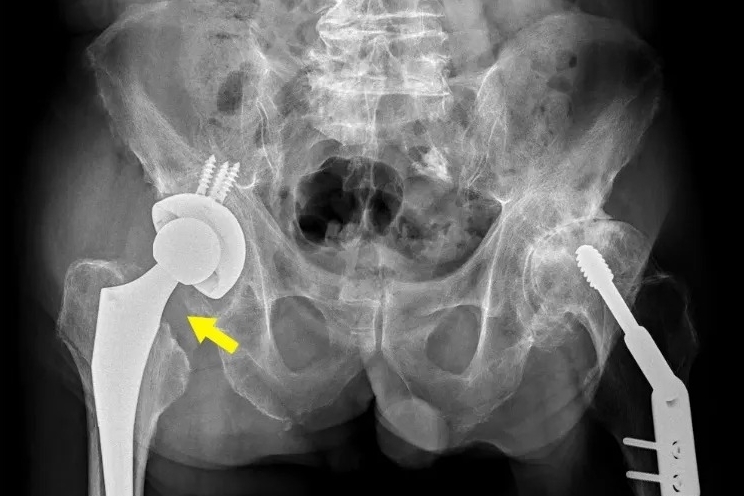

施男最終接受「前外側式人工全髖關節置換術」,手術後當天下午即可下床走動,隔天便能在病房外行走。醫師表示,此術式切口小、恢復快,可同時修正腿長不一的問題。施男術後兩週便能拄拐杖外出,疼痛與喀喀聲皆消失,生活品質明顯改善。